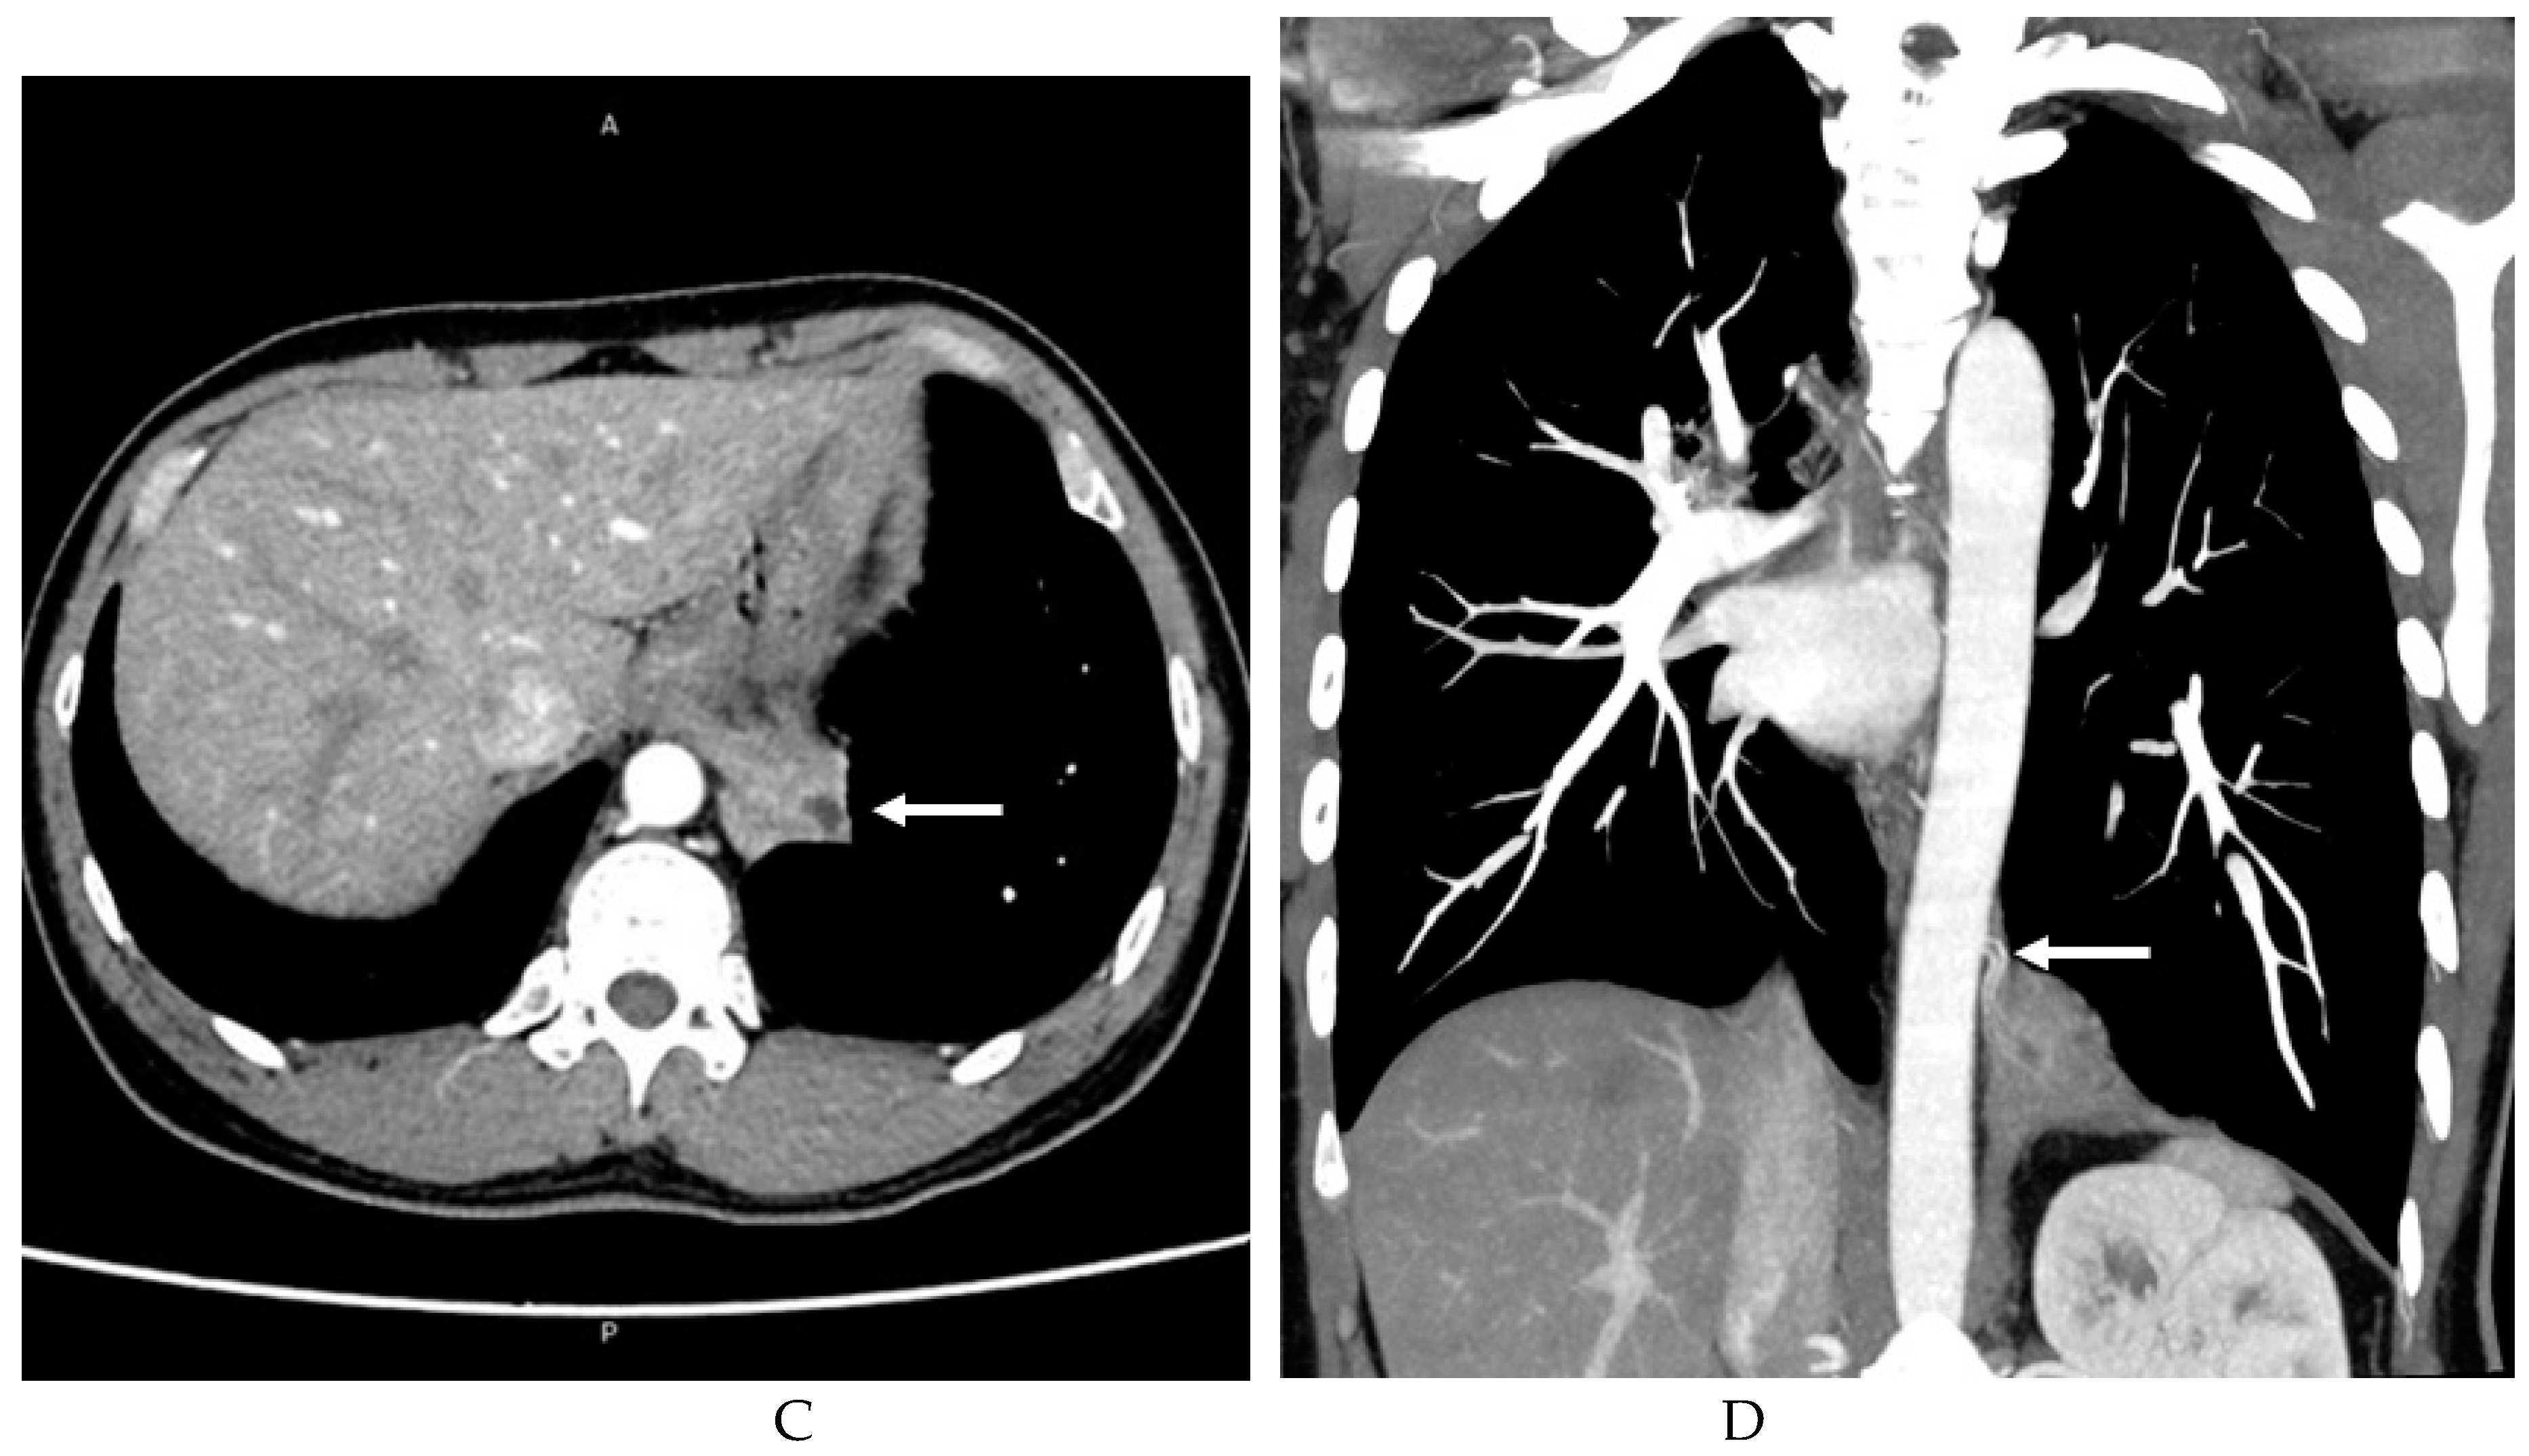

3.2. Imaging appearances of CTPA

- Long, Q.; Zha, Y.; Yang, Z. Evaluation of pulmonary sequestration with multidetector computed tomography angiography in a select cohort of patients: A retrospective study. Clinics. 2016, 71, 392–398. [Google Scholar] [CrossRef]

- Yue, S.W.; Guo, H.; Zhang, Y.G.; Gao, J.B.; Ma, X.X.; Ding, P.X. The clinical value of computer tomographic angiography for the diagnosis and therapeutic planning of patients with pulmonary sequestration. Eur. J. Cardiothorac. Surg. 2013, 43, 946–951. [Google Scholar] [CrossRef] [PubMed]